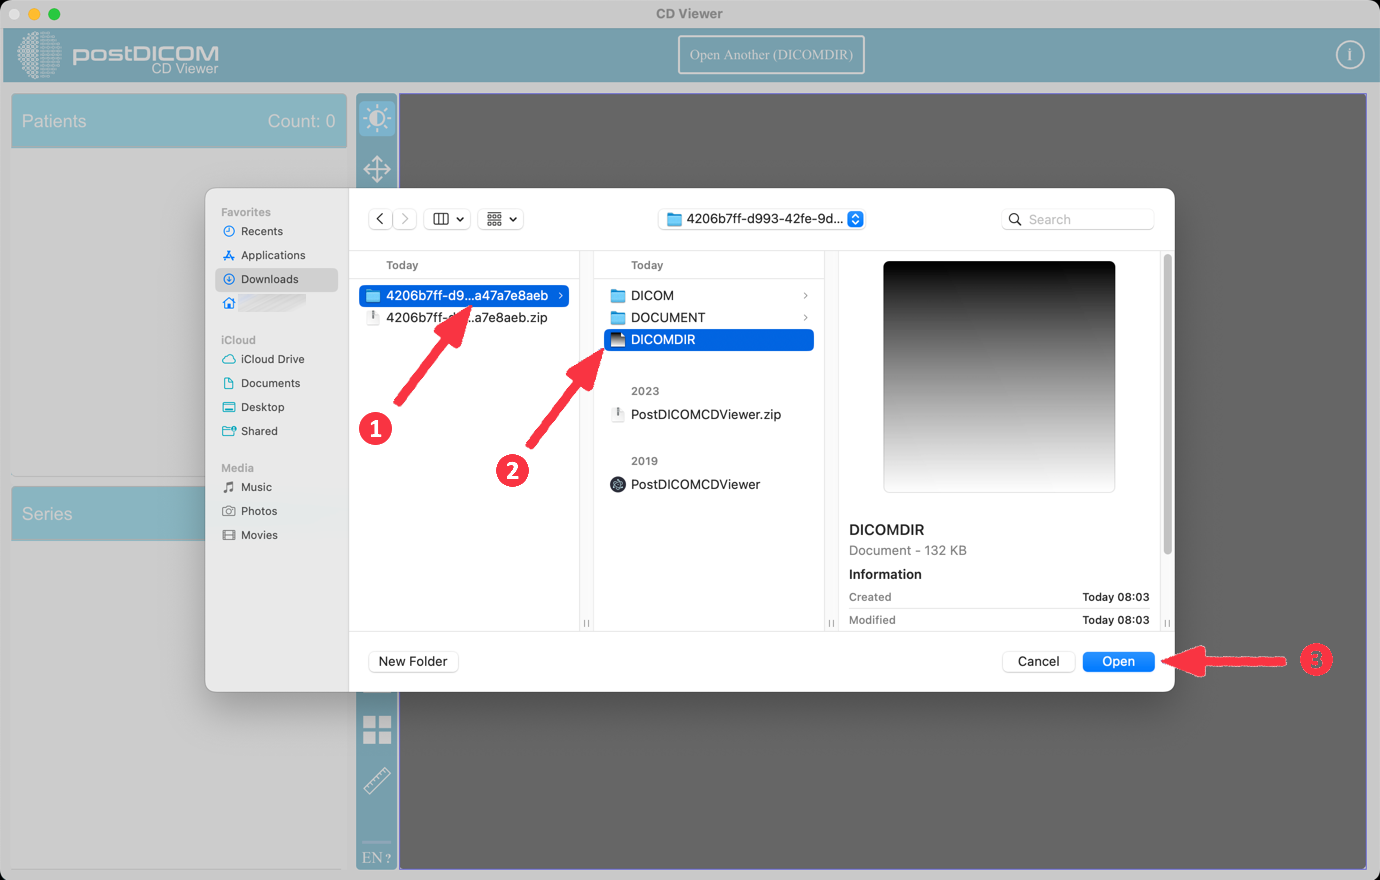

Click the 'Open Another (DICOMDIR)' button at the top of the application. Then select DICOMDIR file.